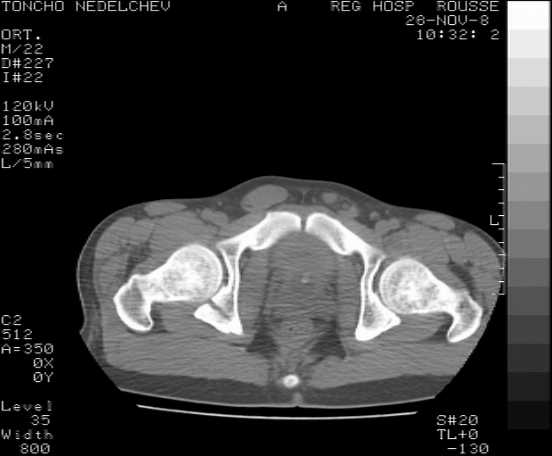

Re: Acetabular fracture

Here are some more axial images. What is your opinion as for the timing of the operative treatment?